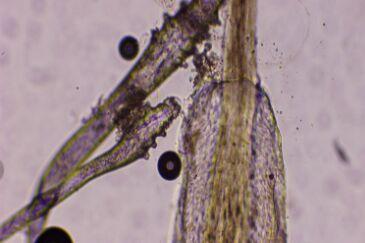

“过年三件套”美甲、美发、种睫毛爆火,可第一批受害者也出现了。有人种睫毛后眼睛遭罪,像浙江省的王女士,种完睫毛眼睛反复痒,滴眼药水也不好,一查竟是睫毛上长了螨虫,引发了睑缘炎。原来种睫毛时,器械若没严格消毒,螨虫就容易侵入眼睑毛囊。 还有杭州22岁的王女士,做了延长甲片,骑电动车摔跤,手指触地,延长甲片断裂,结果食指指骨骨折、甲床破裂。看来“过年三件套”虽能变美,但也得悠着点,在美丽和健康之间找好平衡,别让变美成了受罪。